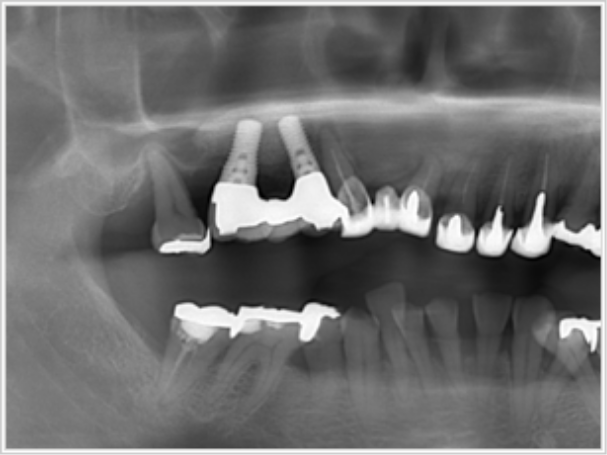

上顎全部欠損

- 治療期間

- 7ヶ月間(インプラント入れてから完成まで

プラスチック

・奥歯(銀歯)

計8本 240万円(税込)